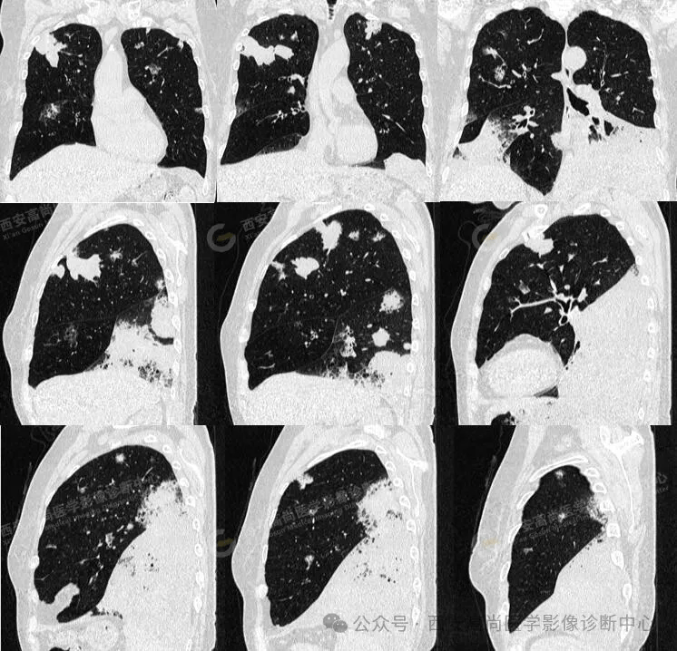

pet/ct病例—肺粘液腺癌,历经3年余终确诊【西安高尚医学影像诊断中心